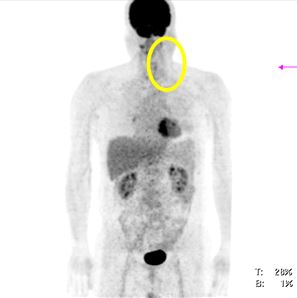

v Chụp PET/CT sau điều trị: khối hạch cổ trái tan biến hoàn toàn, không thấy tăng hấp thu FDG tại cơ quan bộ phận khác của cơ thể.

Hình 2: hình ảnh chụp PET/CT sau điều trị cho thấy khối hạch cổ trái tan biến hoàn toàn, không thấy tăng hấp thu FDG tại cơ quan bộ phận khác của cơ thể.